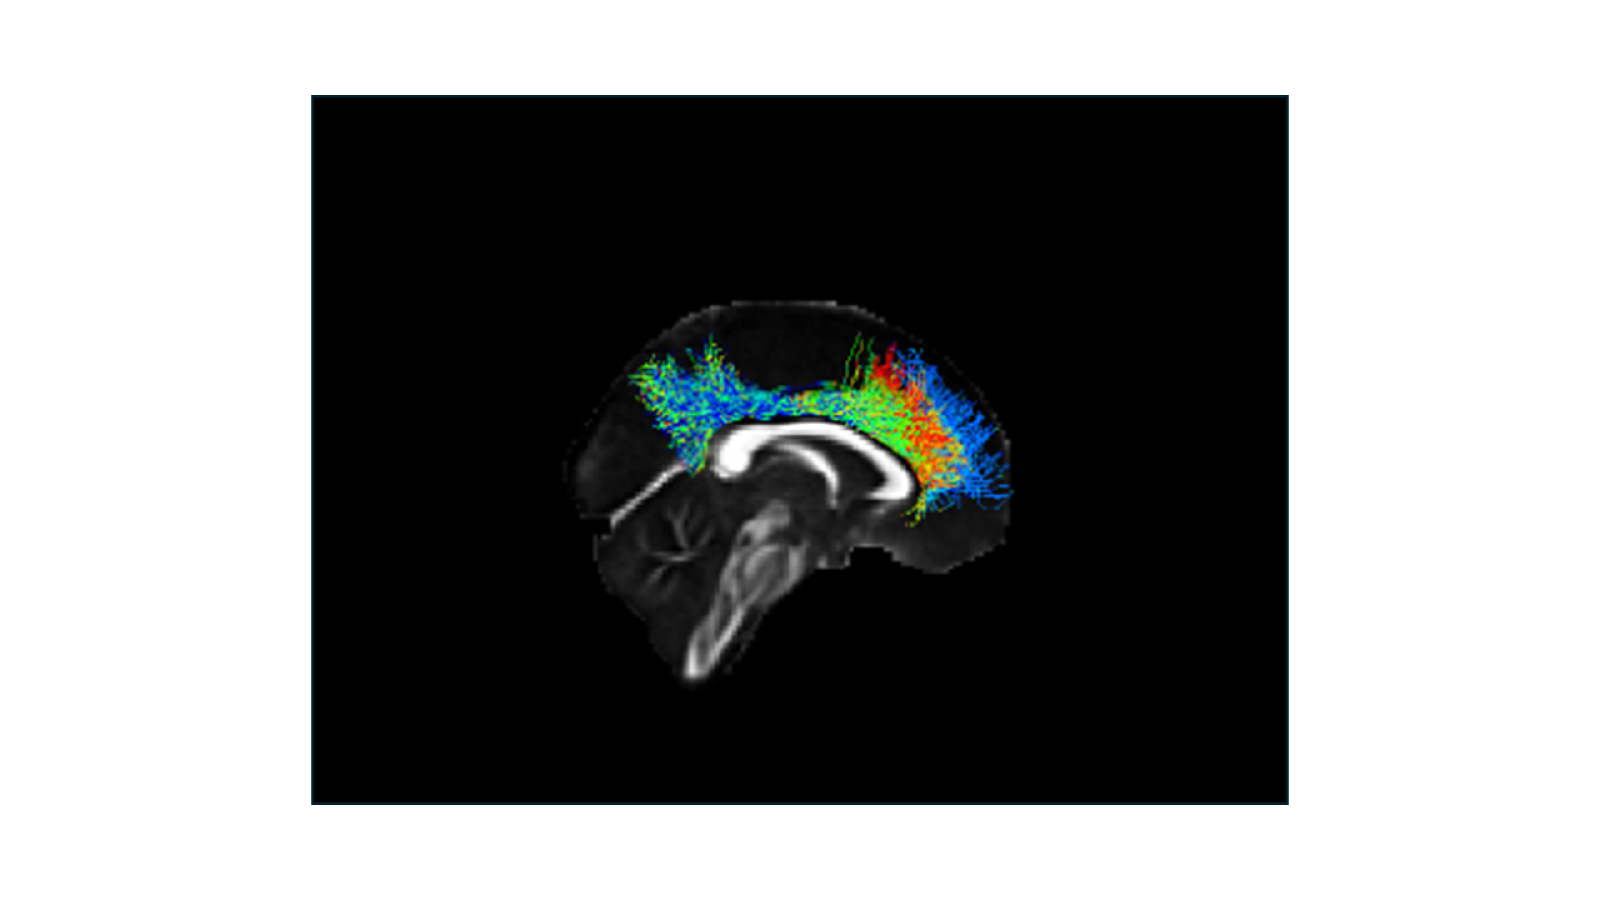

Childhood brain injury can lead to lasting damage to the brain’s white matter pathways. This image shows the “cingulum bundle”, a pathway that runs from the back of the brain to the front. We found that, after a serious brain injury, children and adolescents continued to have damaged white matter (depicted in red/orange color) compared to healthy children, even a year or more after the injury occurred. Our advice: WEAR A HELMET!